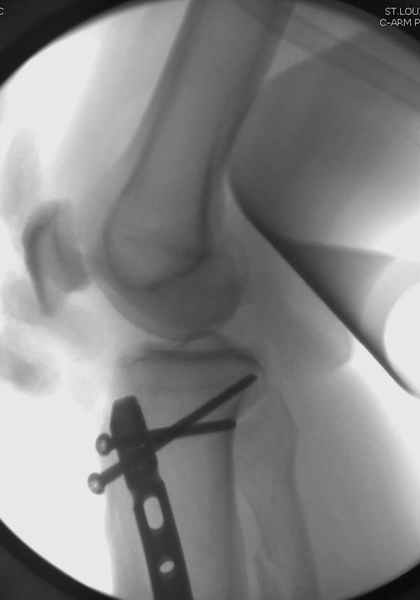

При такий спирали задний край tibia может быть сломан - нет ли этого в данном случае? На всякий случай можно было ввести 1-2 винта 4,5 мм спереди назад мимо гвоздя. Хотя самый дистальный блокирующий винт, возможно, зацепил этот отломок. А какой тут диаметр гвоздя и locking винтов?

Если там и правда сломан задний край, то лучше с нагрузкой подождать, даже будь больной полегче.